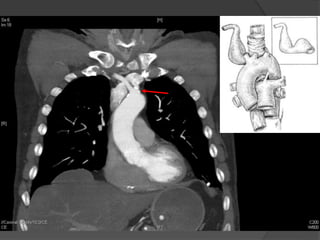

Suites Post-operatoires: CTA

 Aucunes

endofuites ou

migration

 Exclusion

complete et

thrombose de

artere lusorienne

ainsi que le

diverticule

Cas1

 Aucunes complications post-operatoire

 Duree hospitaliere:

 6 jours

 Suite post-opératoire:

 Asymptomatique (resolution de la toux)

 CTA a 4 mois post TEVAR